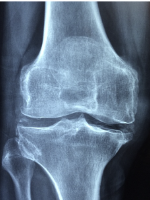

무릎 관절염 증상 무릎 관절염 원인 치료방법 관리방법 등 무릎 관절염에 관한 정보를 정리해드리도록 하겠습니다. 무릎 관절염은 무릎 관절에 염증이 생기는 질환으로, 통증과 붓기, 운동장애 등의 증상을 유발합니다. 무릎 관절염에는 여러 가지 원인이 있지만, 가장 흔한 것은 퇴행성 관절염입니다. 퇴행성 관절염은 노화나 과부하로 인해 무릎 연골이 닳아나가는 과정에서 발생하는 질환입니다. 연골은 무릎 뼈 사이에 있는 연한 조직으로, 뼈의 마찰을 줄여주고 충격을 흡수하는 역할을 합니다. 연골이 손상되면 뼈와 뼈가 직접 부딪치게 되어 통증이 생기고, 염증 반응이 일어나서 붓기가 발생합니다.